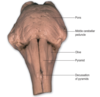

What are visible on the ventral surface of the medulla?

Prominent longitudinal columsn, the pyramid which run either side of the ventral median fissure.

Lateral to the pyramid lies an elongated elevation, the olive, within which lies the inferior olivary nucleus

What delineates the transition from medulla to pons on the ventral surface of the brainstem?

The transverse system of fibres (the transverse pontine fibres) that originate from cells in the ventral pons and pass through the contralateral middle cerebellar peduncle to enter the cerebellar hemisphere. This massive system obscures the underlying pyramidal tracts

Features of the ventral surface of the midbrain?

Consists of a large column of descending fibres on either side, the crus cerebri or basis penduculi.

The two crura are separated by the interpeduncular fossa (basal cistern).

The crus cerebri is continuous with the internal capsule of the cerebral hemispherse and consists of corticobulbar and corticospinal fibres.